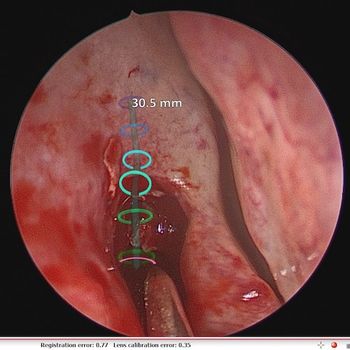

Augmented reality could become a valuable teaching tool for the next generation of surgeons.